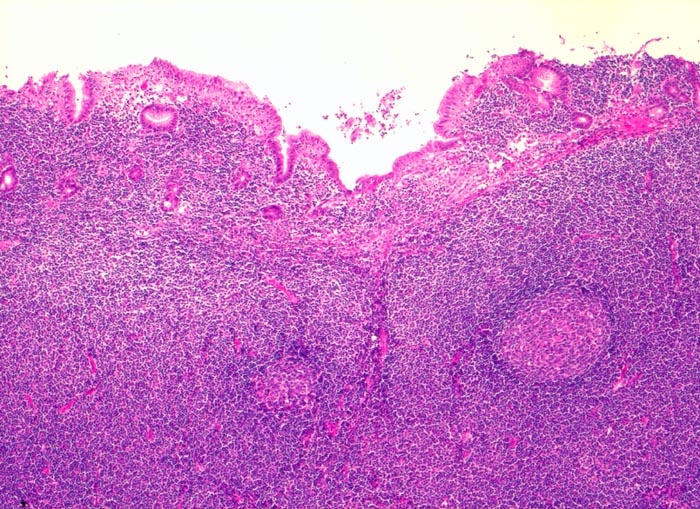

PathoPic ID 3424 - extranodales Marginalzonenlymphom vom MALT-Typ

extranodales Marginalzonenlymphom vom MALT-Typ

Magenantrum

Ausbreitung der Tumorzellen in der Marginalzone um und zwischen

reaktiven Sekundärfollikeln. Infiltration von Mukosa und Submukosa.

73 jährige Patientin mit chronischer Helikobakter-Gastritis. Magenbefall ohne Lymphknotenbefall.

Oft multifokales Tumorwachstum (Gefahr der falsch negativen Diagnose wegen Trefferfehler bei Biopsie).